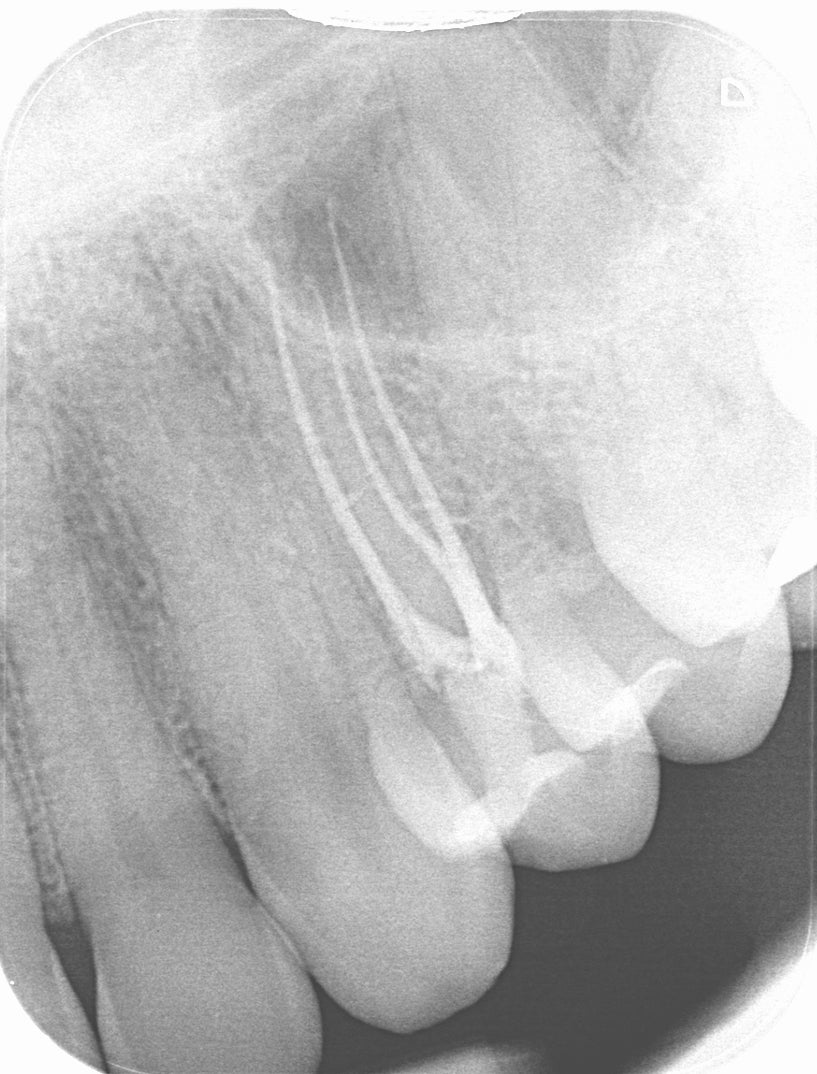

Evidence confirms that fluid-tight obturation is critical to long-term success, as it seals the root canal space to prevent the ingress of microorganisms and the egress of lingering bacteria into periradicular tissues. According to a systematic review in the Journal of Endodontics, poor obturation quality—specifically inadequate length or density—is a leading cause of post-treatment disease. Expert consensus underscores that while disinfection is paramount, a seal and high quality coronal barrier is necessary to maintain a healthy periapical environment.